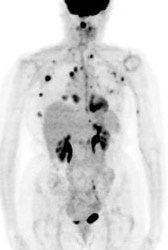

Multifocal breast cancer: The FDG PET exam below is from a patient with a large left breast cancer. The PET exam demonstrated several sites of tracer uptake in the left breast (black arrows). Retrospectively, multiple tumor foci could be identified on the CT scan (white arrows). The presence of multifocal breast cancer can significantly alter patient management. |